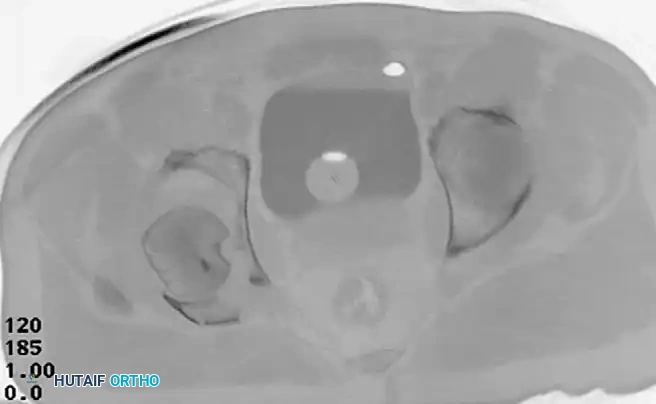

Incarcerated Intra-Articular Fragments

Following the closed reduction of a hip dislocation, a post-reduction CT scan is mandatory. While small avulsions of the ligamentum teres sequestered deep in the cotyloid fossa may be observed, any osteochondral fragment lodged between the articulating surfaces of the femoral head and the acetabular dome necessitates urgent surgical excision and joint irrigation.